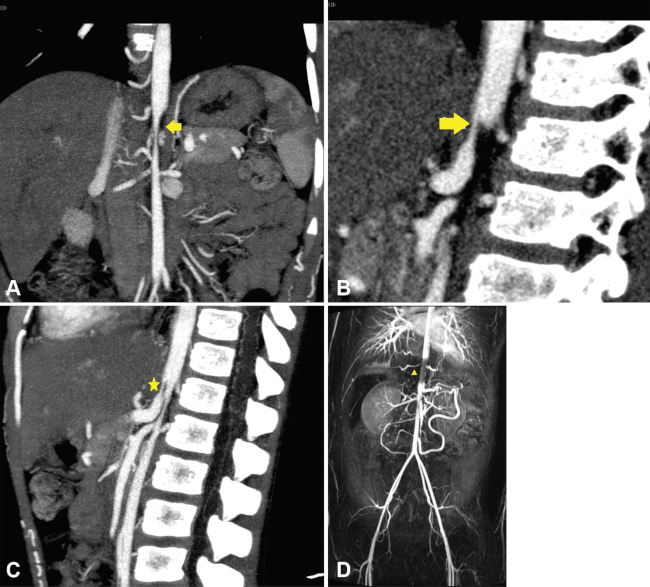

Arteritis de Takayasu

Es una enfermedad inflamatoria crónica de etiología desconocida que afecta a vasos de mediano y gran calibre, como la aorta y sus ramas, los troncos supra-aórticos. Predomina en mujeres de mediana edad. La aorta abdominal está comprometida con más frecuencia, en segundo lugar, la porción descendente de la aorta torácica y, con menor frecuencia, el cayado. La anatomía patológica demuestra granulomas e inflamación de la pared arterial, con infiltración y proliferación de células mononucleares en la capa adventicia, seguido de fibrosis y calcificación en etapas crónicas. Los hallazgos que se evidencian en la TCMD incluyen:

Engrosamiento concéntrico de la pared, que en los estadios tempranos de la enfermedad se observa en “doble anillo” (realce de la capa íntima inflamada y el realce de las capas media y adventicia)

Trombosis

Estenosis

Oclusión

Además, se puede observar ectasia, aneurismas y úlceras (►Fig. 1).1,7

La clasificación en base a los hallazgos angiográficos divide a la enfermedad en cinco tipos con diferentes niveles de afectación de la aorta y sus ramas, haciendo distinción especial cuando se afectan las arterias coronarias y/o pulmonares, y es útil en la planificación quirúrgica (►Tabla 1).8